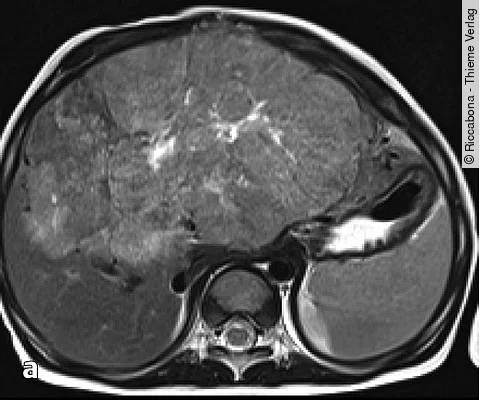

Quiz der WocheAuflösung: Säugling mit Gelbsucht und aufgeblähtem Bauch

Der Junge hat ein Hepatoblastom.